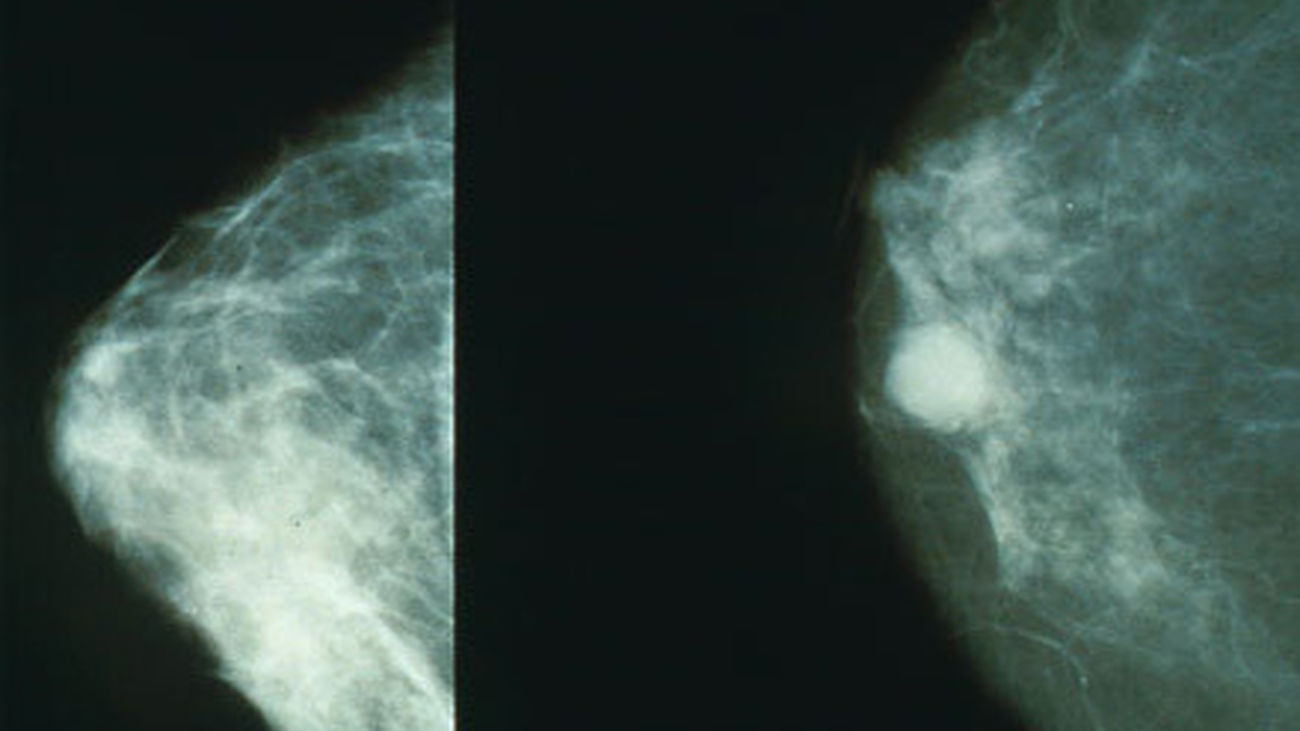

La Consejería de Sanidad de la Comunidad de Madrid ha puesto en marcha un programa piloto de estudios genéticos para la mejora en el tratamiento del cáncer de mama, denominado Proyecto Predictores Genómicos en Cáncer de Mama (PREGECAM), ha informado la Comunidad en un comunicado.

El pilotaje, que se inició en mayo de 2012 ya ha contado con la participación de 195 mujeres que, por las características del tumor detectado, tienen un perfil adecuado para participar en el programa voluntariamente y de acuerdo con el criterio de su especialista.

El objetivo del PREGECAM es determinar la utilidad de los tests genómicos para personalizar el tratamiento de la patología en cada paciente. La información que aportan los tests pueden indicar si un tratamiento de quimioterapia será o no eficaz para el tratamiento del cáncer de mama, o si es más aconsejable un tratamiento hormonal, mucho menos agresivo.

Por tanto, pueden ayudar al oncólogo a establecer el tratamiento más adecuado en función de la genética de la paciente basándose en el concepto de medicina personalizada. Los tests también aportan información sobre las posibilidades de que la paciente sufra una recaída.

El pilotaje da la posibilidad al oncólogo de utilizar los tests genómicos Oncotype DX y Mammaprint, que han sido objeto de varios estudios de coste-eficiencia en diferentes países con buenos resultados. La Consejería de Sanidad financia la totalidad de los tests solicitados por los oncólogos durante el pilotaje.